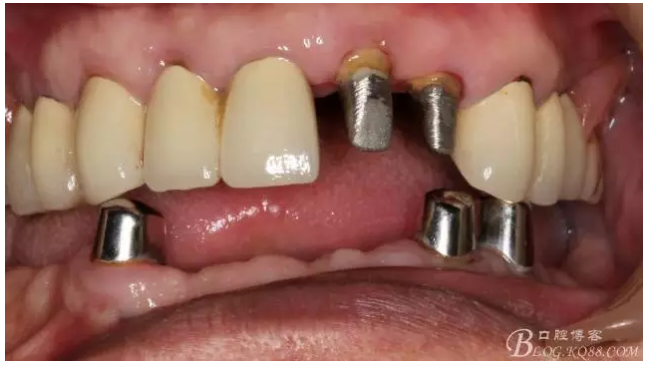

早期的病歷大約在2009年左右,那時(shí)只做了下頜的套筒冠

當(dāng)時(shí)勸病人上頜也做了修復(fù),但是病人感覺這樣還可以,把下面牙齒鑲好再說,雖然上面的牙齒不同程度的牙齦萎縮,都有些松動(dòng),但是患者年歲已高,只做下頜修復(fù)。囑咐病人半年復(fù)診一次,可是病人這一走就是2年,來要求制作上牙的修復(fù)

還要有足夠的牙本質(zhì)肩領(lǐng),大家現(xiàn)在可以看到患者的下頜套筒冠還是非常好的

修復(fù)后照片,

患者的口腔衛(wèi)生保持的不好,有大量的軟垢附著,